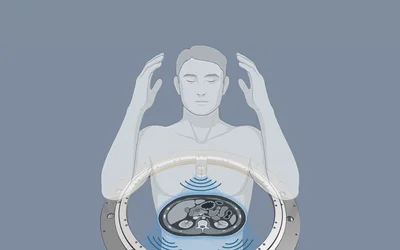

Nordic Bluetooth LE Audio-powered Doppler device delivers dependable wireless connectivity in surgical and clinical applications

Remington Medical's VascuChek employs Nordic's nRF5340 SoC to provide low latency, high sound quality for reliably monitoring patient blood flow